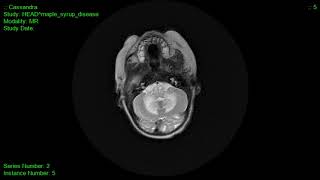

• Video Case Reviews – Real-world cases across all modalities: X-ray, CT, MRI, Ultrasound, and Nuclear Medicine.